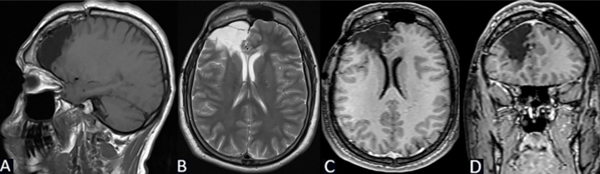

Se puede observar en la Figura 7 la RM postquirúrgica de cerebro.

Figura 7. Caso 2. RM de cerebro postquirúrgica: cambios anatómicos del lecho quirúrgico en región temporal derecha con lesión isquémica parenquimatosa secuelar occipitoparietal derecha hipointensa en T1 e hiperintensa en T2. La administración de gadolinio no pone de manifiesto refuerzos patológicos significativos. A) Secuencia T1, corte sagital. B) Secuencia T2, corte axial. C) Secuencia T1 con contraste, corte coronal. D) Secuencia T1 con contraste, corte sagital.